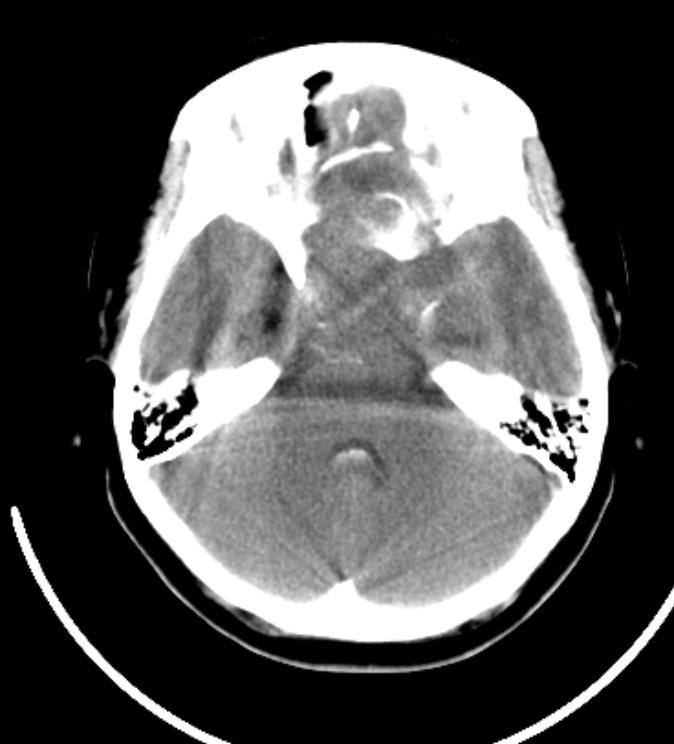

f 13y,右侧眼视力下降1年多,头疼。

鞍上见一巨大椭圆形、分叶状高、等、低混杂密度肿块,明显占位效应,侧脑室额角、三脑室及四脑室内见高密度区,脑室系统扩大。

考虑:鞍上颅咽管瘤伴出血破入脑室系统、争性梗阻性脑积水。